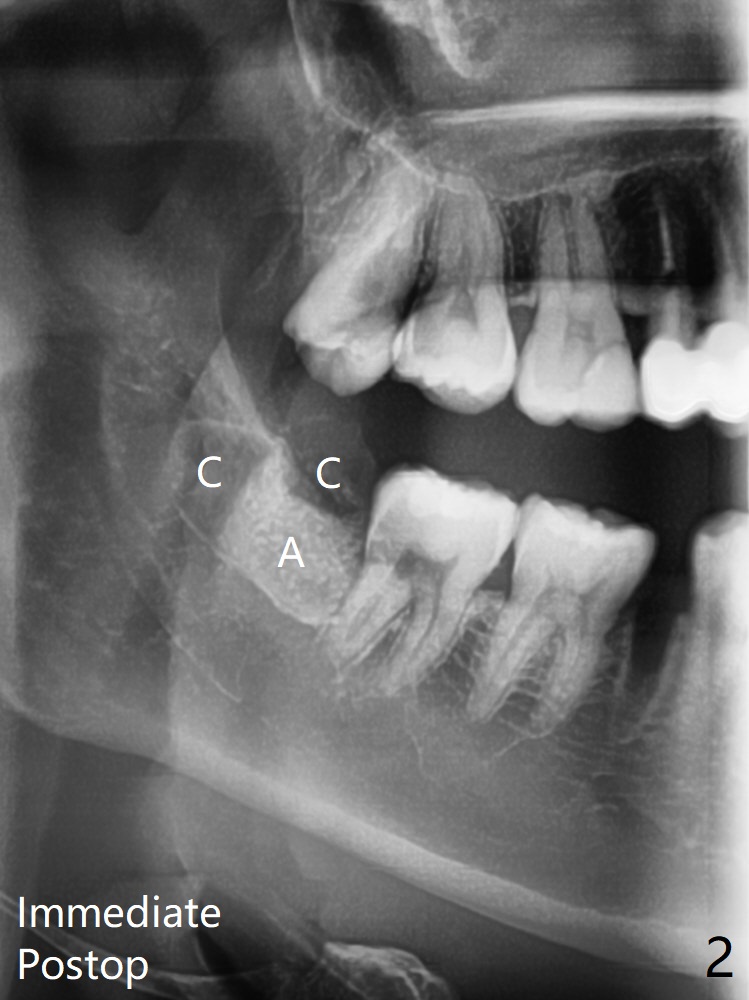

A 36-year-old nervous woman with left TMJ click agrees to have #29 with caries (<) and 32 extracted in preparation for orthodontic treatment (crowding, Fig.1). With 1/2 of Collagen plug placed in the apical portion of the socket, Bond Apatite (1 cc, A) is placed, followed by the other 1/2 of Collagen Plug coronally (Fig.2). Sutures are removed 22 days postop; the wound heals.